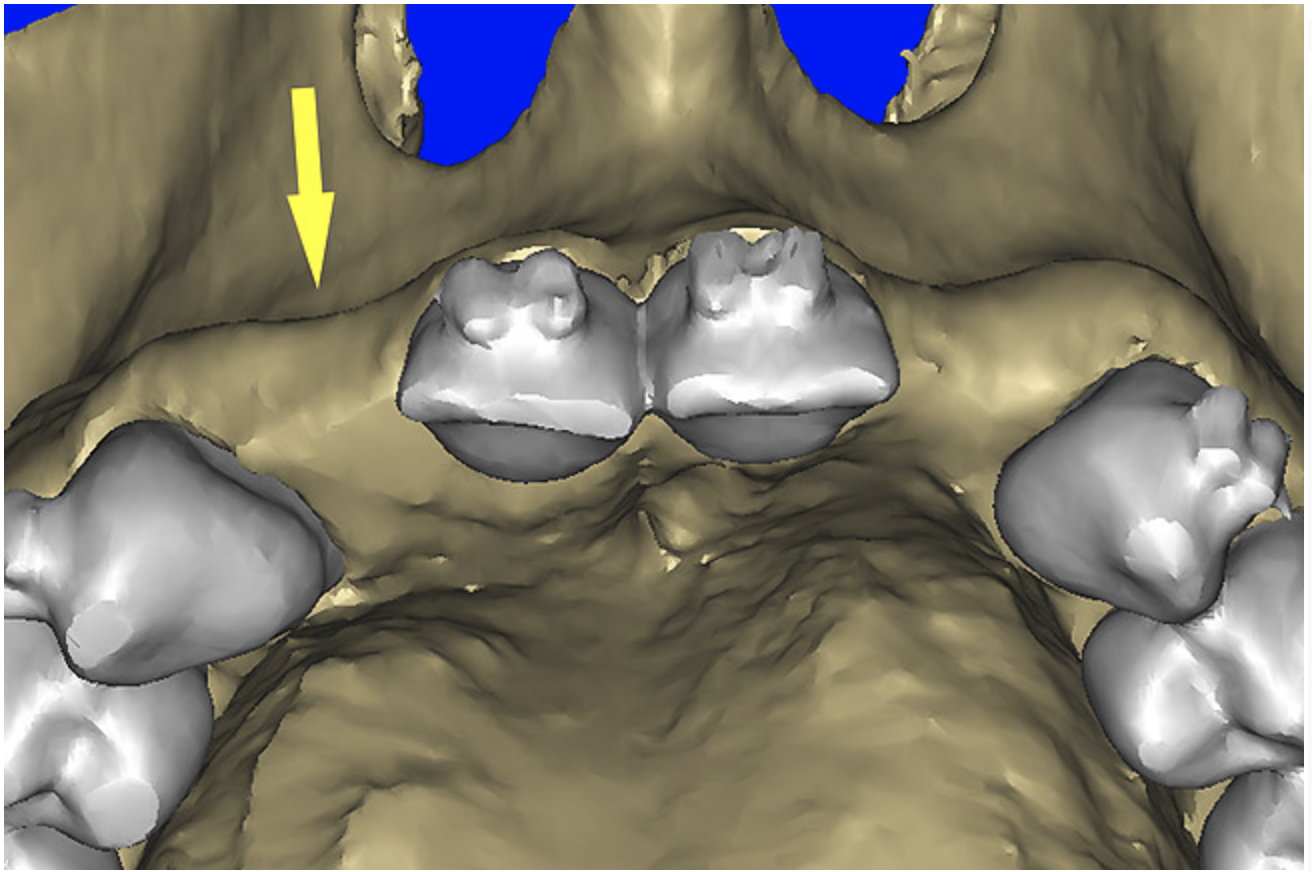

Using different masking (segmentation) and threshold Hounsfield unit values, several new 3D bone volumes can be created which offer invaluable information. To help determine the final position of each implant a new bone model was created with a Hounsfield unit value of 1480, which eliminated all but the densest objects included in the scan data. (Results may vary depending on the CBCT machine used.) The inner and outer layers of bone were removed, leaving the underlying enamel and root structure of the teeth (Figure 8A). After the bone had been stripped away, the root inclinations were examined closely. The most striking findings confirmed the rotated position of the right central, while revealing the slight mesial dilaceration of the root apex, which converged on the space needed for the path of the potential implant (Figure 8B). The schematic shapes of the proposed implants were visualized for the right and left lateral spaces in different rotations of the 3D maxillary arch. It was at this point that a determination was made as to the appropriate implant shape and type that would fit the available space while avoiding encroachment on adjacent tooth roots. A tapered design implant (Tapered Screw-Vent®, Zimmer Dental, www.zimmerdental.com) was chosen from the large virtual library. With the SIMPlant software, the virtual library contains data from dozens of implant manufacturers and realistic computer-aided design representations as seen in Figure 9A through the translucent bone. The position of the left implant can be visualized with adequate mesial-distal distance between adjacent tooth roots (Figure 9B) and a more delicate placement (Figure 9C).

Figure 8a  By using the masking feature, the inner and outer layers of bone were removed virtually, revealing (A) the enamel and root structure of the teeth and the rotated position of the right central and (B) slight mesial dilacerations of the root apex.

Figure 8a

Figure 8b  By using the masking feature, the inner and outer layers of bone were removed virtually, revealing (A) the enamel and root structure of the teeth and the rotated position of the right central and (B) slight mesial dilacerations of the root apex.

Figure 8b